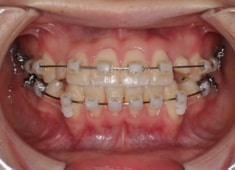

治療開始時

治療中